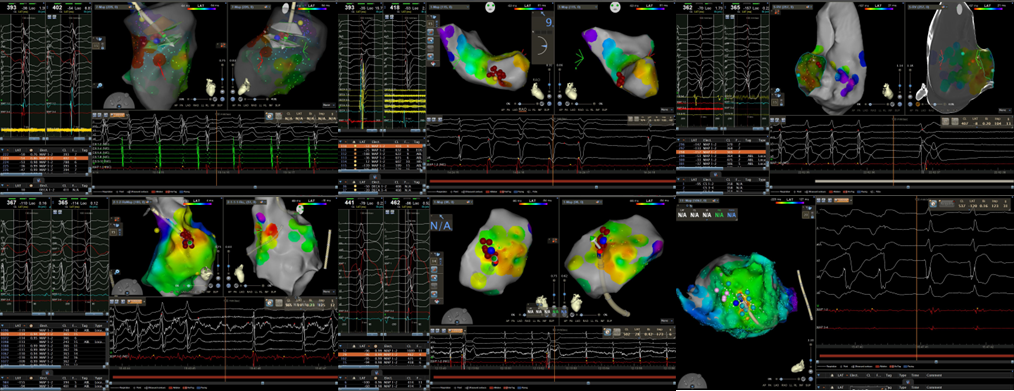

心血管内一科起搏电生理团队在面临急诊手术高风险及高不确定因素情况下,应用急诊射频消融方式顺利终止上述患者无休止室速,改善患者血流动力学及心脏功能。

针对医院集中面临的上述问题,心内一科王军奎主任、官功昌副主任牵头,心内一科起搏电生理团队赵娜主任医师、崔倩卫副主任医师、李博涛主治医师,研究生胡苏、王婷及进修医生王鹏制定了急诊室性心动过速射频消融的流程和方案。整个流程和方案得到心脏外科心脏超声组、介入诊疗手术室的大力支持。

传统认知中,射频消融术只能择期进行,并且仅适用于血流动力学稳定的患者。目前,在成熟完备的标测技术和手段加持下,对血流动力学不稳定的无休止室速行急诊射频消融术能转服窦律,为后续原发疾病诊治或ICD(体内除颤器)植入争取机会。